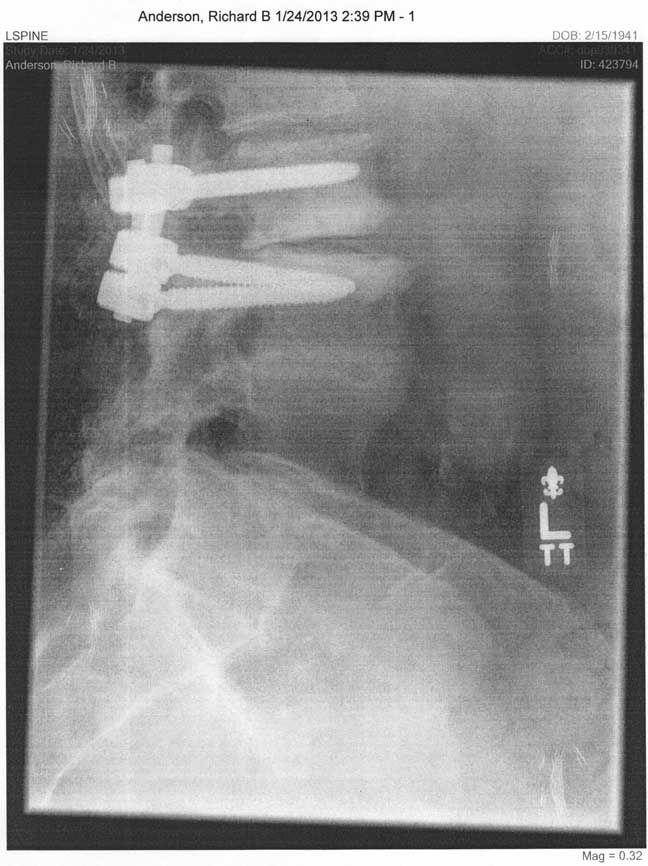

• In January, 2013, Bob performed a second lumbar fusion, removing the old hardware and installing bolts and screws at the next level up.

Fusion hardware, extending and replacing the work from 2008, in January, 2013